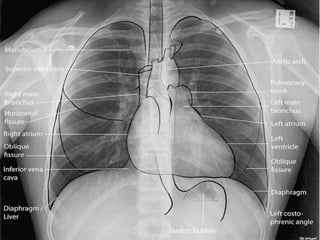

 This patient presented to the emergency department

for increasing fatigue and shortness of breath.

 CXR

 Shows-

 A complete white out of the right

 lung .

 Trachea is central.

Trachea remains central in position

 USG of same patient-

 This is the appearance of consolidated lung (in this case, cancer). Normal lung is air filled and not

readily visible with ultrasound, but in consolidation as fluid fills the lung and displaces air the lung is

easier to visualize with ultrasound.

 In this image its easy to see the difference between collapsed lung (from cancer) and pleural fluid, but

in some cases complex effusions can be more difficult to distinguish. You can look for air

bronchograms (small bright reflectors from air trapped in the lung), or doppler can be used to

visualize small pulmonary vessels.